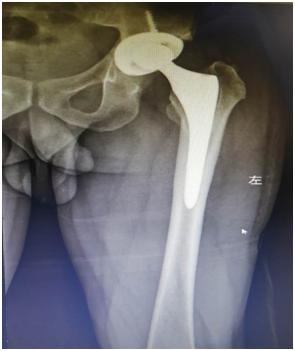

手术前的x光成像

经过一段时间的康复和观察, 2020年4月23日,张先生再次入院,阆中市人民医院骨科汪军、何涛、吕彬林三位医生通力合作为张先生行“关节翻修术”。手术中将张先生左侧的人工髋关节间隔器取出,并按生理角度安放人工髋关节。2个小时后,患者顺利完成了手术并被送回病房,术后患者恢复良好,并于2020年5月18日出院。

人工关节翻修后